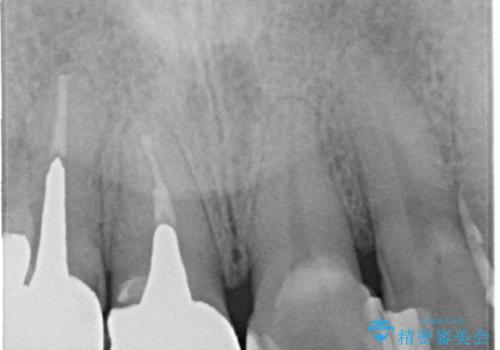

- 以前治療した上の前歯の不自然な保険のかぶせ物を自然なものにしたいとのことで来院されました。

右上の前から1番目から3番目までの歯のかぶせ物を土台から再治療することとなりました。

金属の土台を、ファイバーコアという歯根にやさしく白いものに交換して、かぶせ物をオールセラミックにしました。